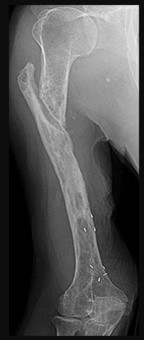

Figures 13a and 13b are the radiographs of a 57-year-old man who is seen in the emergency department. He has been experiencing left thigh pain for 2 month. Four years ago he underwent laparoscopic nephrectomy and states that he has been disease free since the resection (although he has not seen a doctor in 2 years). The pathogenesis of osteolysis in renal cell carcinoma metastatic to bone includes secretion of parathyroid hormone-related peptide (PTHrP), transforming growth factor-B (TGF-B), and vascular endothelial growth factor (VEGF), which directly cause overexpression receptor activation of nuclear factor kB ligand (RANKL) on which cells?

Tumor cells in renal cell carcinoma interact with the bone microenvironment to drive bone destruction and tumor growth by secreting factors such as PTHrP, TGF-B, and VEGF. These factors stimulate the host osteoblast, causing overexpression of RANKL, which in turn causes bone resorption through stimulation of osteoclasts. RANKL expression is upregulated in many types of metastatic cancer to bone, and blocking the RANK/RANKL interaction prevents progression of metastases.

Other actions of RANKL include triggering the migration of human tumor cells that express RANK. RANK and RANKL are expressed in metastatic renal cell carcinoma, and their presence strongly signifies potential recurrence. The use of denosumab, which binds and inactivates RANKL, has its basis in these findings in renal cell carcinoma.